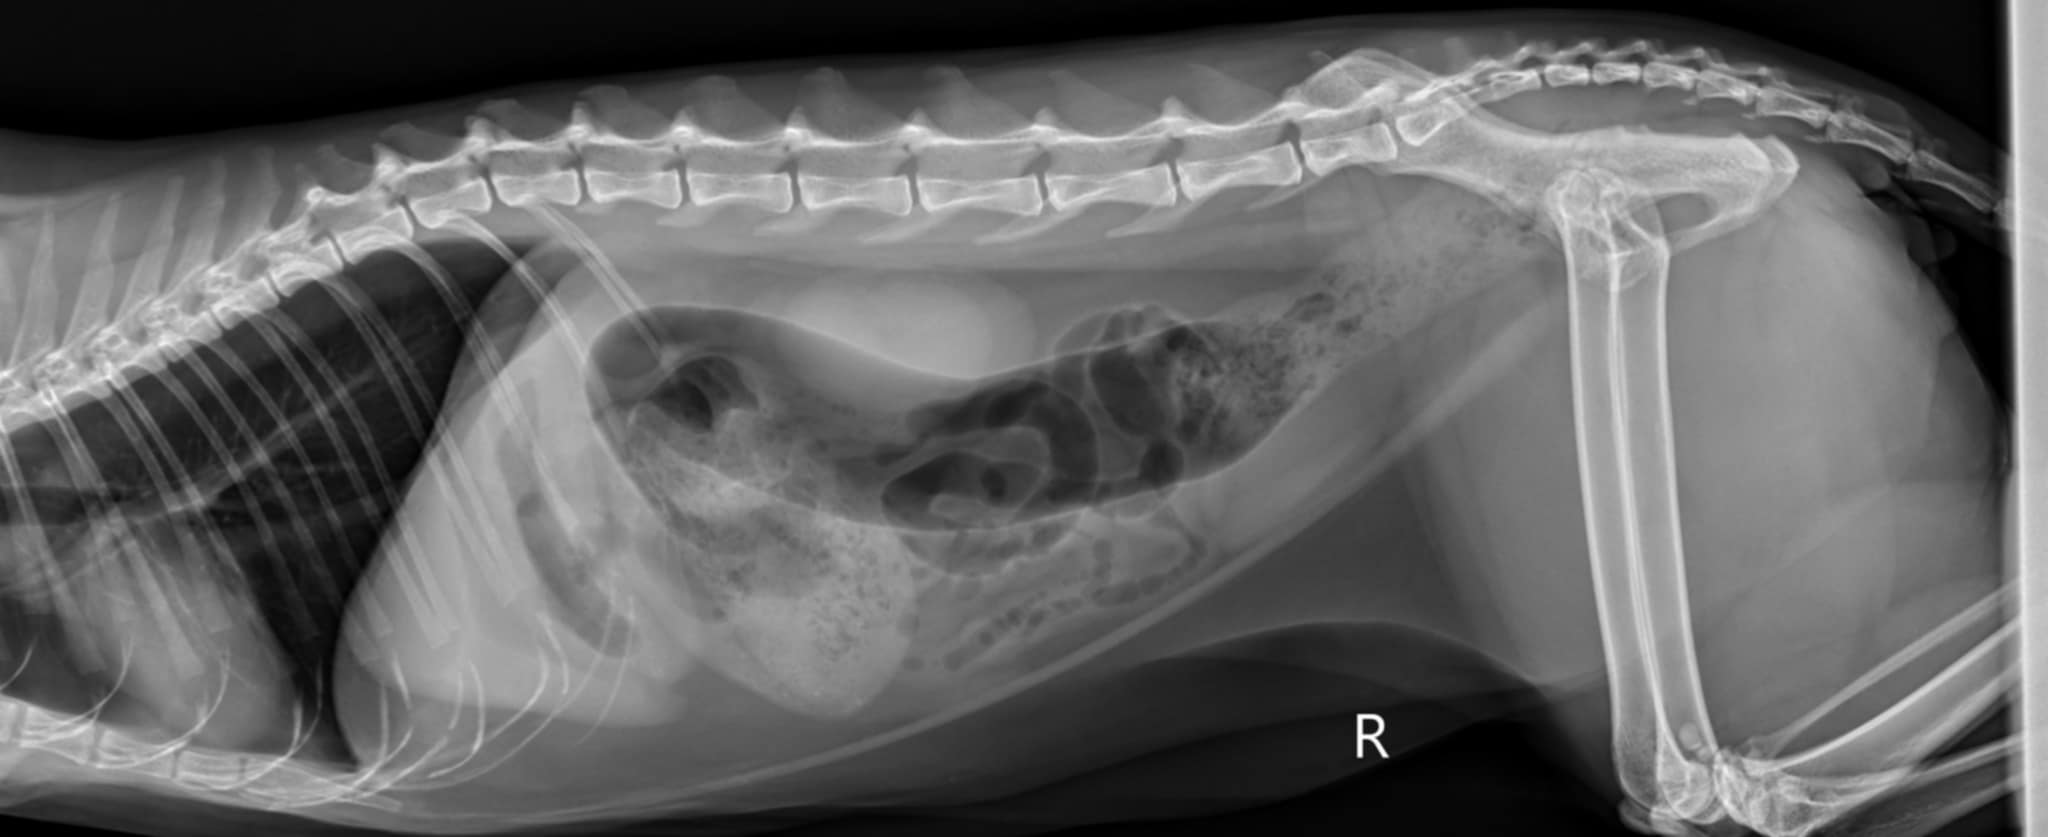

For over two years, Bunker has been battling chronic IBD (inflammatory bowel disease) and possible lymphoma scares, which has meant ongoing treatments, medications, and many unexpected vet visits along the way.